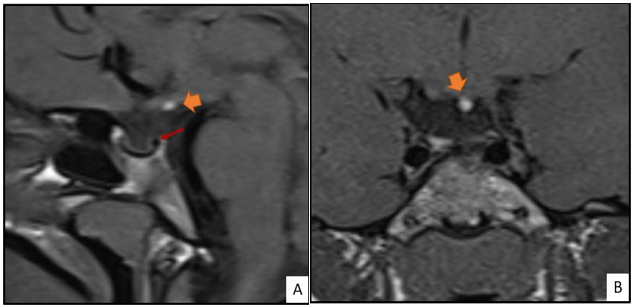

Secondary Hypopituitarism Due to a Pituitary Stalk Interruption: A Case Report

Fatima Zohra Benbrahim, Majda Ankri, Nazik Allali, Siham El Haddad and Latifa Chat. 7(9): 01-04.